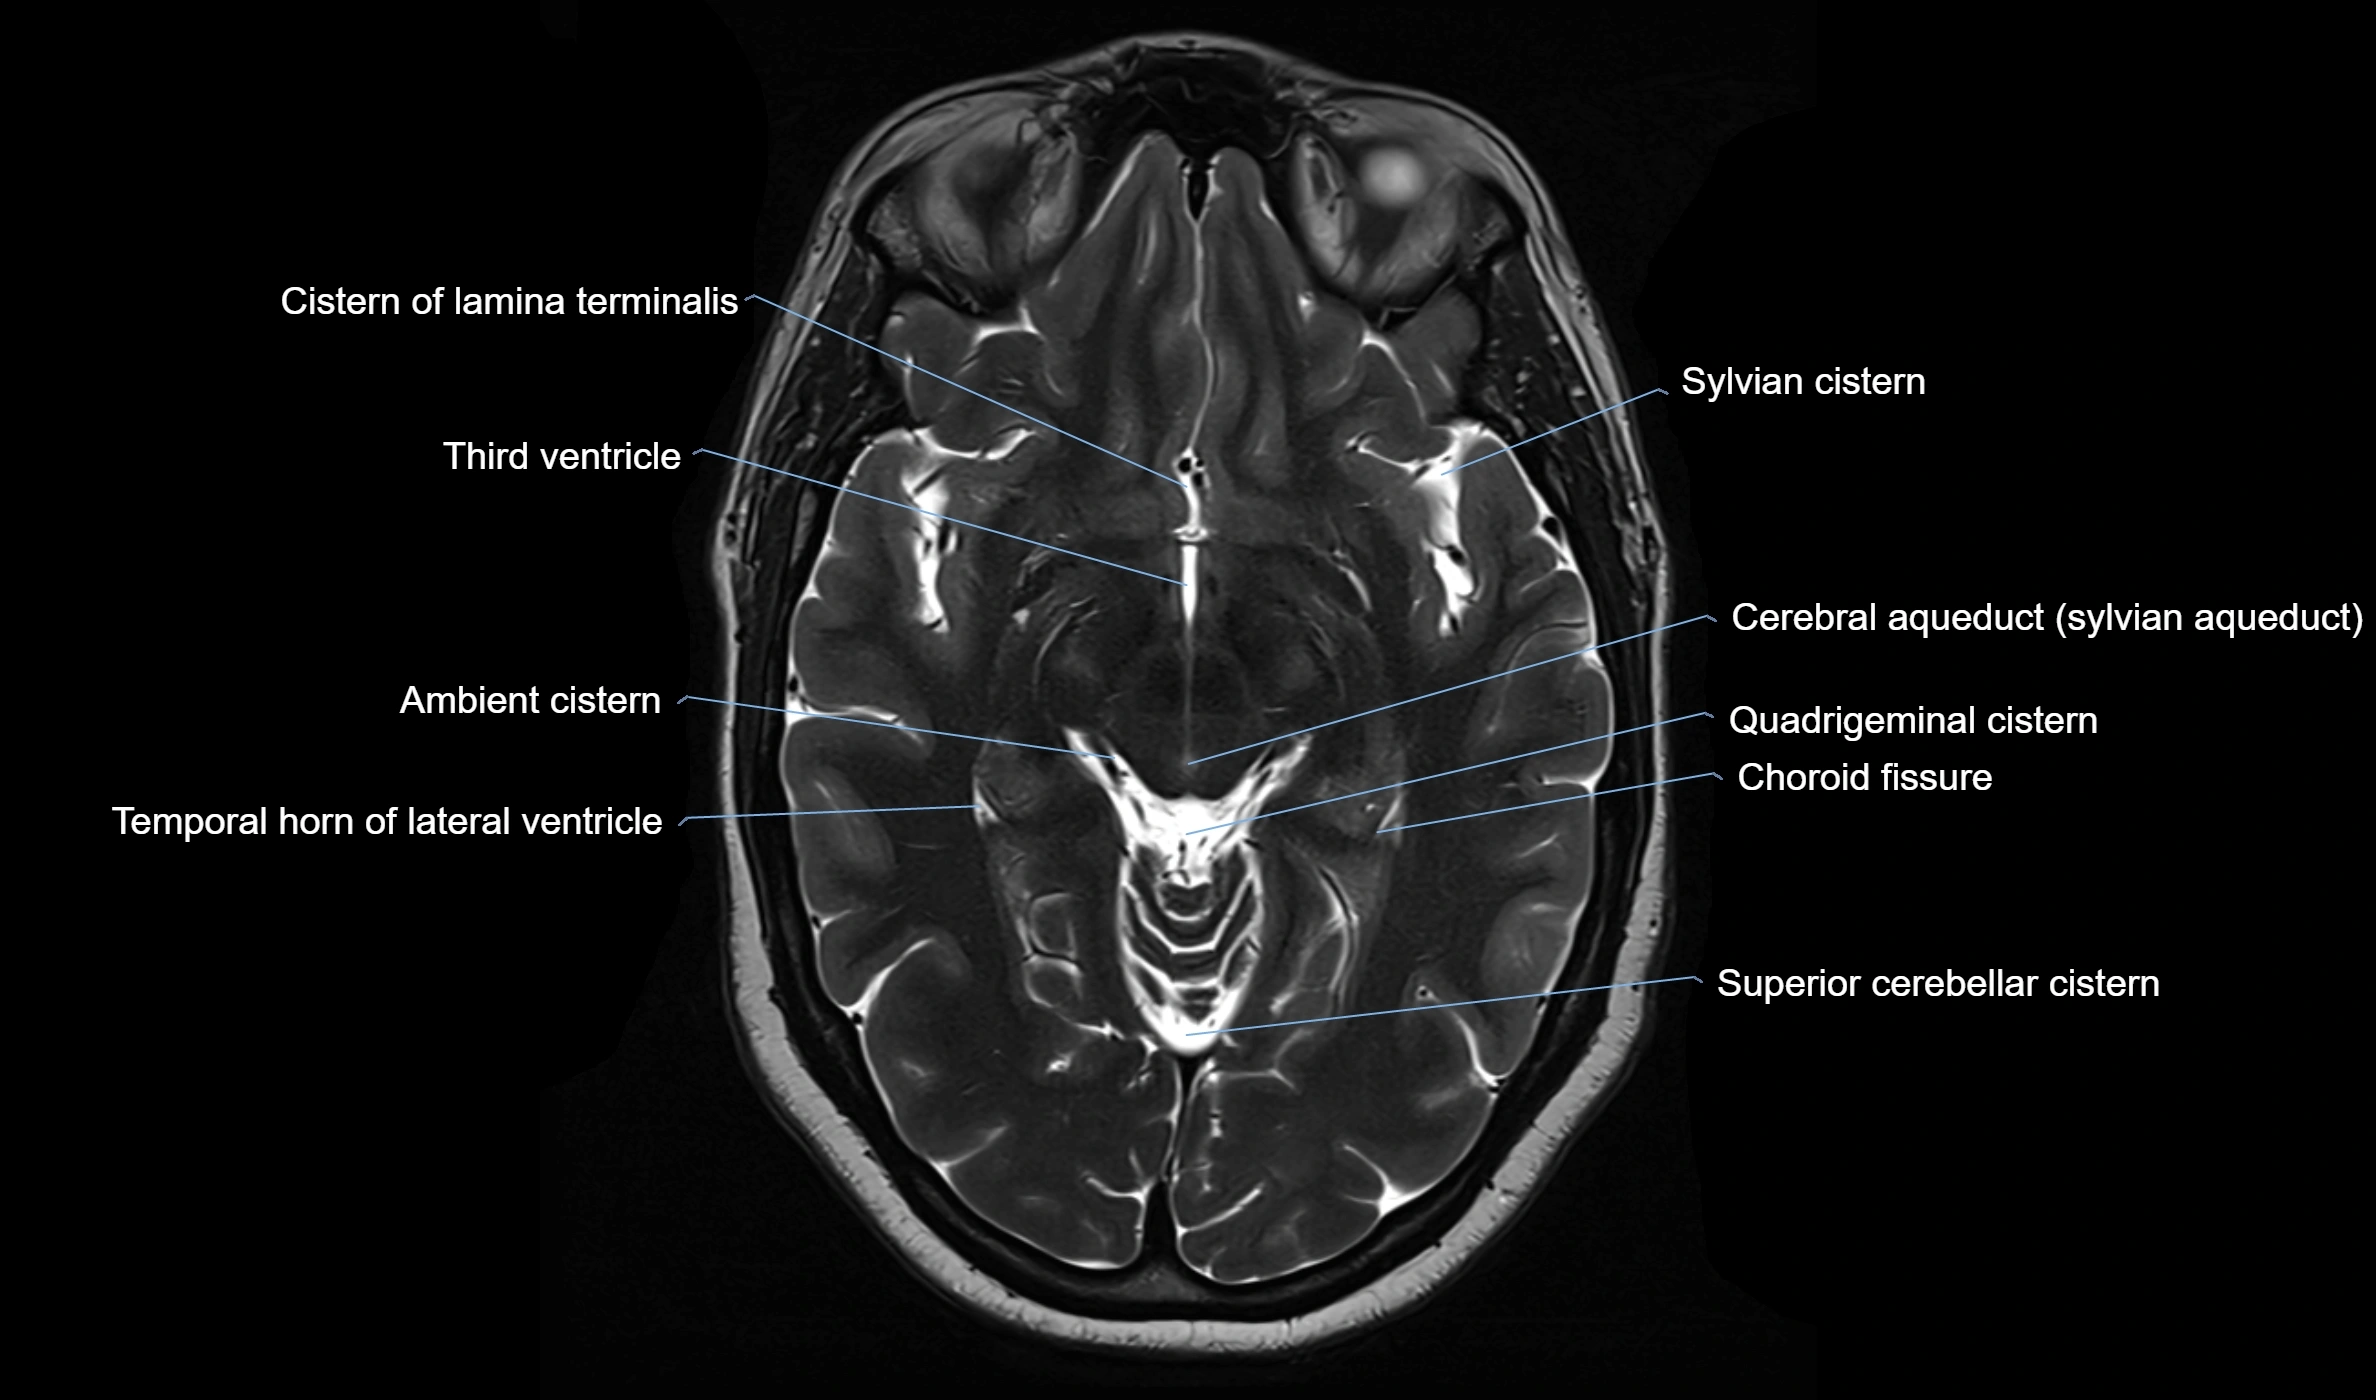

Ambient cistern

The ambient cistern is a paired, narrow, and elongated subarachnoid space located bilaterally along the lateral aspect of the midbrain. It serves as a conduit between the interpeduncular cistern anteriorly and the quadrigeminal cistern posteriorly. This cistern houses critical neurovascular structures, including parts of the posterior cerebral artery, superior cerebellar artery, trochlear nerve (cranial nerve IV), and the basal vein of Rosenthal. It plays an important role in the circulation of cerebrospinal fluid (CSF) and provides an anatomical corridor for various vessels and nerves passing around the midbrain.

MRI Appearance

• T2-weighted images:

• The cistern is hyperintense (bright) due to the high water content of CSF.

• Encapsulated vessels and nerves are seen as flow voids or hypointense lines within the bright background.